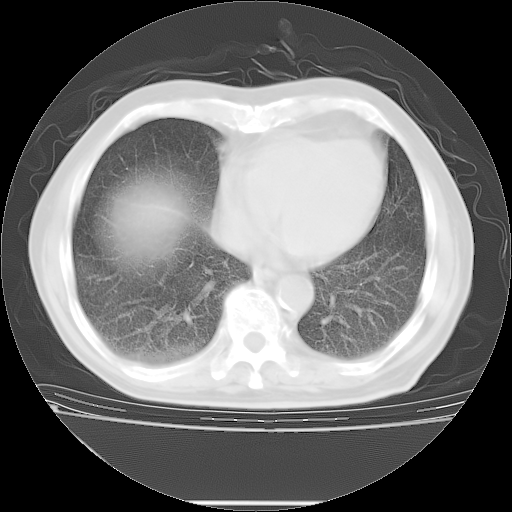

今天复查肺部CT,发现双肺广泛磨玻璃样改变。所以我把3月19日和5月9日相隔50天的肺部CT上传。请大家会诊。

5月9日肺部CT(在4月27日齐鲁医院肺部CT描述部分肺组织磨玻璃样改变,12天后肺组织广泛磨玻璃样改变)

2009年5月9日肺部CT

大致读了系列胸部CT:纵隔窗无明显异常,肺窗:从4、27至今:主要是双肺中下野外带可见毛玻璃样改变,目前处于急性肺泡炎阶段,至于原因考虑1、结替组织或胶原血管性疾病所致?2、恶性疾病如恶组在肺部所致的表现或细支气管肺泡癌?3、药物或其它原因如肺蛋白沉着症所致肺泡炎目前不太可能?总之,明天就去请我院的呼吸科、感染科、血液科和临免专家会诊哈。